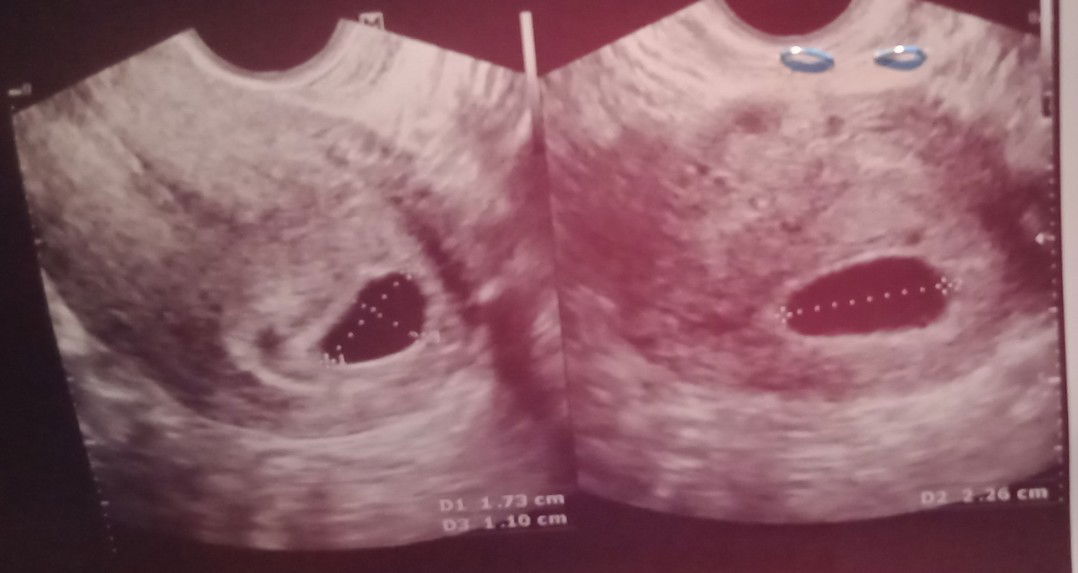

My naka experience n Po b s inyo po n nag pa xtray for medical.. tpos after mga ilan weeks mala2man n buntis po pla? Kasi MAY 7 to 10 Ang regla Ko po.. tpos MAY 21 nagpa xtray po ako Kasi mag work po sana ako.. tpos nong JUNE 10 ng PT akoh nag positive poh sya.. tpos po nag pa trans V po ako noong June 23 e2 poh Ang lumabas 6weeks exactly poh ako non.. bkit ganito po ang ultrasound ko Po eehh.. nata2kot po Kasi ako pra smin ng baby ko Po..

tama po 6 weeks kau based dn po kasi un sa LMP na May 7. ang mganda pong gwin, inform nyo po OB nyo para by 20-24weeks, maadvice nya po kau mgpaCAS to see if may problem sa baby. tingn ko po hindi need mgworry kasi sa akin po dati naexpose dn po ako sa radiation nung 5weeks pregnant then ngCAS normal and now mg2yrs old na sina kambal ok naman sila. ang sabi naman ng radiologist, super liit lng ng radiation sa xray.